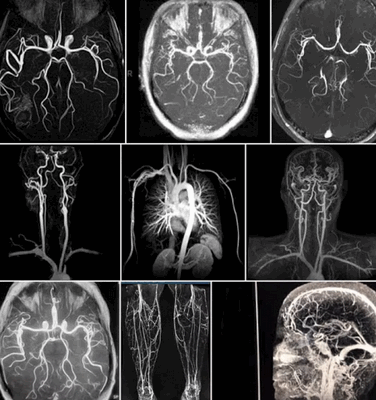

- МР-ангиография — высокоэффективный метод быстрой оценки кровотока в аорте и периферических артериях. Магнитно-резонансный томограф позволяет просматривать изображения сосудов в двухмерном и трехмерном режимах.

МР-ангиография — оценка проходимости кровотока, состояния даже мельчайших сосудов в двухмерном и трехмерном режимах.

Какие сосуды можно исследовать с помощью МРТ?

С помощью МРТ можно оценить сосуды любой локализации. Существует несколько модификаций диагностического метода:

МР-венография. Чаще всего оба варианта назначаются, чтобы оценить состояние сосудов головного мозга и шеи.

МРТ сосудов средостения.

Томография сосудов шеи.

Томография структур головного мозга. При наличии жалоб или подозрения врача. Когда есть подозрения на поражения вещества ЦНС, применяется обзорная или точечная модификация томографии. Она позволяет оценить полушария, а также глубоко залегающие структуры (гипофиз, ствол, гипоталамус). Труднодоступные участки. Они видны хуже, потому назначают МРТ на более мощном аппарате. От 1 Тл мощностью. С помощью комплексного подхода можно обнаружить заболевания церебральных структур (рассеянный склероз, опухоли и прочие), а также самих сосудов.

Модификацию способа для прохождения выбирает лечащий врач на основании показаний, гипотез и личных соображений.

Делается ли МРТ всех сосудов одновременно?